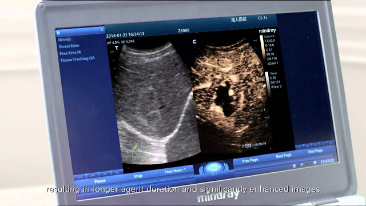

???? ??? 3T Transducer Technology?

M9? ???? ?? ???? ?? ??? ??? ?????? ?????? ???? 3T ????? ??? ??? ????. ??? ??? ??? M9? ?? ??? ?? ?? ?? ? ?? ?? ???? ?? ???? ??? ?????.

Echo Boost?

??? ?? ??? ?????? ??? ??? ?? ???? ??? ??? ?? ? ?? ??? ???? ?? ?? ??? ?????? ?? ??? ????? ???? ?? ?? ?? ?? ??? ?? ?? ?? ??? ???? ?????.